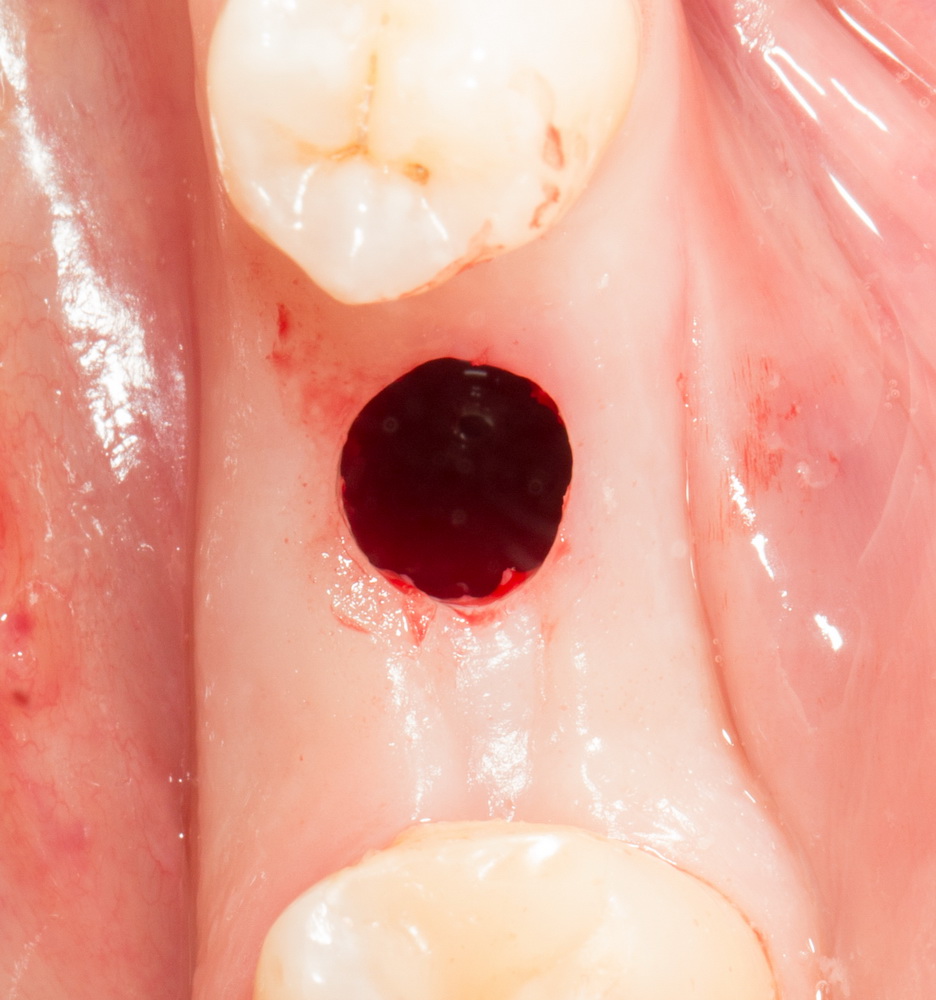

Остеопластические операции: факторы успеха. Часть II.